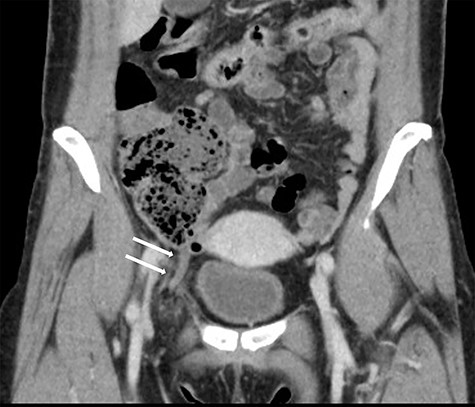

A 1.5-cm intraumbilical incision was made under general anesthesia, and the subcutaneous tissue and the anterior rectus sheath were dissected. The right rectus abdominis was moved to the lateral side, and a 12-mm trocar was inserted into the extraperitoneal space. Thereafter, two 5-mm working trocars were inserted into the midline of the lower abdomen. The insufflation pressure was set at 10 cm H2O. Under a 30-degree telescopic vision, the preperitoneal space was dissected to the inguinal region using an ultrasonically activated device. This revealed the incarcerated hernia sac in the femoral canal (Fig. 2). Because replacing the sac from the femoral canal was difficult, the lacunar ligament was divided. After the femoral ring widened, the sac was safely repositioned into the abdominal space; a 10 × 13 cm mesh (SURGIMESH XD®, Neomedica Co., Roma, Mexico) was placed without tackers to cover the space. Following the preperitoneal approach, we reinserted the 12 mm trocar into the abdominal cavity, and the other trocars were replaced to the left lower abdomen (Fig. 3). Exploration of the abdominal cavity revealed an inflamed appendix, and erythema was clearly recognized in the distal half, proving that appendicitis was caused by compression. There were no findings of necrosis, perforation or abscess formation (Fig. 4). Appendectomy was performed safely. Additionally, mesh repair was confirmed as successful through the peritoneum and there were no other coexisting hernia. The patient recovered uneventfully and was discharged on postoperative Day 3. Histopathological examination revealed moderate inflammation of the appendix.

Preperitoneal view of the incarcerated hernia sac into the femoral ring.